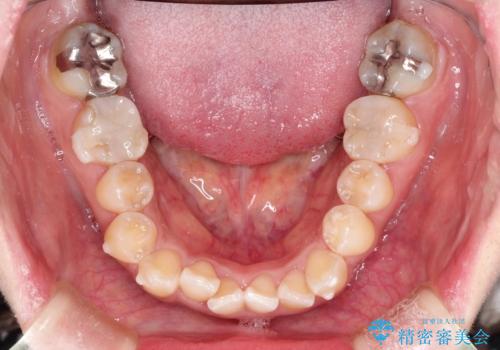

前歯のガタつきをマウスピース矯正で改善! 驚きの効果を体験しよう

- 前歯のガタツキが気になると来院されました。

マウスピース矯正治療を選択しました。

奥歯の噛み合わせは綺麗に噛んでいたため、前歯の叢生(でこぼこ)に集中して治療するように計画しました。

奥歯の噛み合わせは整っていたため、前歯の並びを美しく修正することに専念できました。

前歯のガタツキを改善する治療法として、マウスピース矯正が適していることが多いです。

マウスピース矯正は、金属製のブラケットやワイヤーを使用せずに、透明なマウスピースを装着して歯を移動させる方法です。そのため、目立たず、痛みも少ないです。